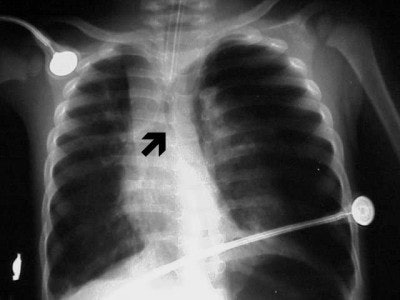

![]() |

| Figure 5 |

In figure 5 we have the chest x-ray of a six-month-old infant with cough, fever, and shortness of breath (SOB). Nine pairs of ribs are visible, the arms are raised above the child’s head, and there is no evidence of rotation. Pathologically, he has right upper lobe aspiration pneumonia (arrow). The darker area in the left lung base was diagnosed as a pneumothorax, cardiomegaly; something is displacing the ET tube to the right. A chest CT was recommended for further evaluation.